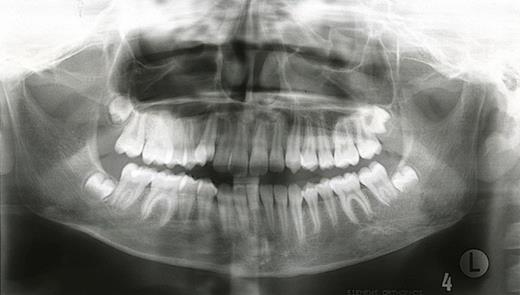

In April 2002 a general dental practitioner referred a 10-year old girl with mandibular asymmetry associated with a 6mm midline shift to the right and a Class 3 skeletal and incisor relationship. Radiographs at initial presentation showed no bony abnormalities and study models were taken, followed by a period of growth monitoring.

In October 2007, the patient represented with a swelling around the left angle of the mandible. Radiographs revealed no abnormalities but oral antibiotics were commenced with the clinical impression being that of osteomyelitis. Over the following month the swelling fluctuated in size, therefore a CT scan was undertaken. This showed a cystic enlargement at the left angle of the mandible with no cortical disruption or soft tissue involvement. With symptoms persisting the patient underwent exploration of the area under general anaesthesia and histopathology (which had previously been negative) now revealed desmoplastic fibroma.

Pre-operative axial CT showing the lesion in the left side of the mandible (denoted by arrows).

A desmoplastic fibroma often behaves in an aggressive manner and macroscopically has a firm consistency with well-defined advancing surfaces that may extend into surrounding soft tissue. It is usually seen radiographically as a well-demarcated, radiolucent lesion. However, CT and MRI offer the best imaging of the lesion(5). The initial facial asymmetry in this case was most likely caused by the desmoplastic fibroma that was not evident on plain radiographic imaging. Further to this the lesion was not clinically active in the 4 years pre-operatively or evident at osteotomy. It was only in the post-operative period that the lesion was diagnosed, albeit following an initial negative histology